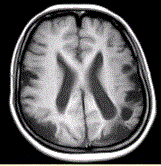

问题 女性,22岁。癫痫发作及智力异常。MRI显示见下图。 该病的诊断为

选项 A.海绵状血管瘤 B.发育性静脉畸形 C.AVM D.毛细血管扩张症 E.动脉瘤 F.硬脑膜动静脉漏 G.moyamoya

答案 G